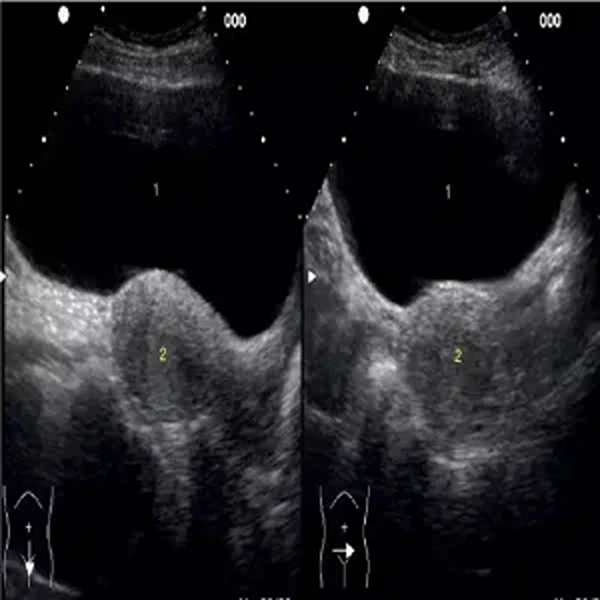

Ecografía Pélvica

La ecografía pélvica es un estudio por ultrasonido que permite evaluar los órganos dentro de la pelvis, como el útero, los ovarios, las trompas de Falopio y la vejiga. Se utiliza para detectar quistes, miomas, infecciones, alteraciones en el endometrio y otras condiciones ginecológicas, además de ser útil en el seguimiento del embarazo temprano. Puede realizarse de forma transabdominal, con la sonda sobre el abdomen, o transvaginal, para obtener imágenes más detalladas. Es un procedimiento seguro, indoloro y fundamental para el diagnóstico y control de la salud reproductiva femenina.